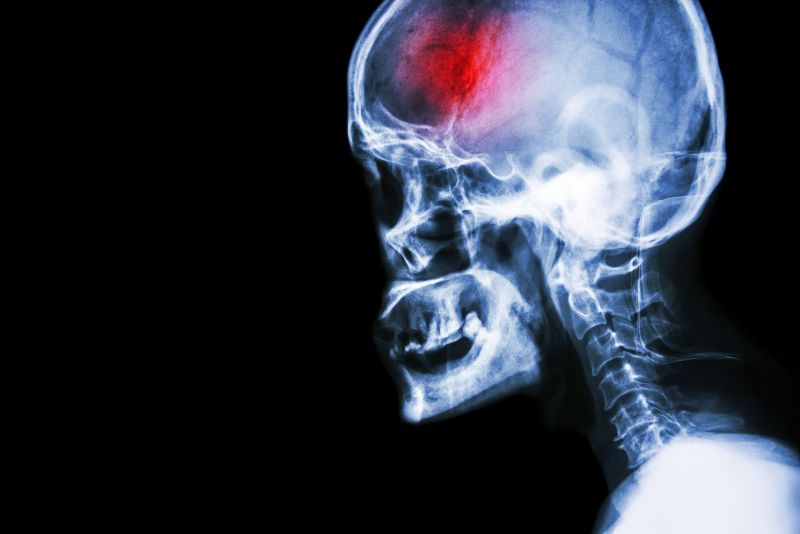

A stroke (previously known as a cerebrovascular accident) when there is a decreased flow of blood to the brain from either a blockage in the blood vessels that supply the brain (ischemic stroke), or a bleed from the blood vessels that supply the brain (hemorrhagic stroke). When the blood flow to the brain is blocked it prevents the brain from getting the needed oxygen and nutrients to function. Without oxygen the brain cells can be permanently damaged or die and the physical and mental functions related to that area of the brain will be affected. A stroke is a medical emergency and rapid treatment is crucial to decreasing the damage caused by a stroke.

Computed Tomography (CT) scan and/or Magnetic Resonance Imaging (MRI) scan: These tests are done on your brain and used to locate the exact location of the stroke and to determine if it has been caused by a blockage or a bleed. These tests can also help rule out other conditions that may be causing symptoms, such as an infection or a brain tumour